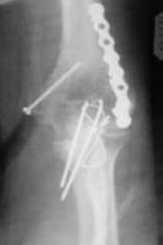

Уважаемые коллеги! Нужен Ваш совет, Подскажите пожалуйста, как можно в дальнейшем этому больному помочь. В марте первая операция, пришлось оперировать на 16 сутки в виду инфицированных садин и анемии. Заживление первичным натяжением,раняя разработка после операции, а через 2 нед болевой синдром,и постепенно движения в локтевом суставе ограничились до полного анкилоза. Повторно через 4 месяца вторая операция" артролиз,удаление оссификатов, удаление фиксаторов, реостеосинтез этой же реконструкционной пластиной и винтом" интраоперационно после удаления оссификатов и фиксаторов обнаружил, что перелом не сросшиеся, поэтому пришлось синтезировать заново. Зажило рана первично, объем движений в локтевом суставе сгибание 70, разгибание160, ротационные движения востановились полностью,вроде бы успокоились. Опять постепенно в течении 8 нед после повторной операции постепенно движения ограничились до 80 - 110, на снимке оссификат. Снимки во вложении, буду рад Вашим советам. Спасибо!С уважением Шухрат.